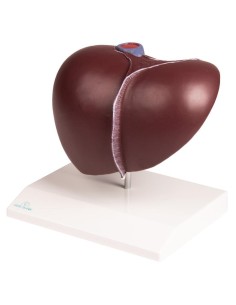

Scopri il Mondo dell’Anatomia con Modelli anatomici di Precisione

Modelli Anatomici Dettagliati per Ogni Necessità

Dal cranio in 22 parti con incastri magnetici ai modelli di colonna vertebrale, da quelli di articolazioni a quelli di cuore, ogni pezzo della nostra collezione è progettato per un’immersione totale nello studio dell’anatomia umana. I nostri modelli, realizzati tramite scansioni di ossa vere, garantiscono un’esperienza tattile autentica e una fedeltà di peso quasi identica agli originali.

Strumenti Didattici Innovativi per l’Educazione e la Pratica Medica

Essenziali per studenti e professionisti, i nostri modelli anatomici sono strumenti didattici che permettono di osservare le strutture anatomiche con precisione, eliminando la necessità di dissezioni o studi invasivi. Sono inoltre utili per spiegare ai pazienti le patologie, rendendo la comunicazione più efficace e risparmiando tempo prezioso.